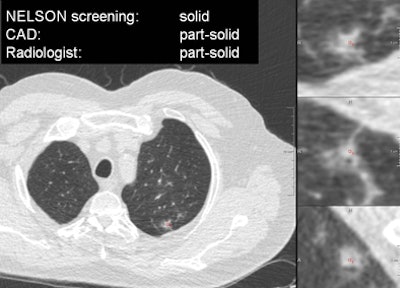

Results of analysis by an expert thoracic radiologist and the CAD algorithm. All images courtesy of Colin Jacobs.The experienced thoracic radiologist slightly outperformed the algorithm in all three categories; however, the radiologist clearly needed help -- saying that he was uncertain about his classification in 25% of the cases, Jacobs said.

Axial slice through the center of the nodule, and on the right are three zoomed-in views in axial, sagittal, and coronal directions. This nodule was classified as solid in the screening database, but both the CAD and the thoracic radiologist judged it to be a part-solid nodule."Nodule characterization is a difficult task, indicated by 25% of the cases in which an experienced radiologist was uncertain about his classifications, especially the differentiation between part-solid and nonsolid nodules. It's a difficult part, both for the CAD and the radiologist," Jacobs said. "And we did not yet assess the interobserver variability of the radiologist."